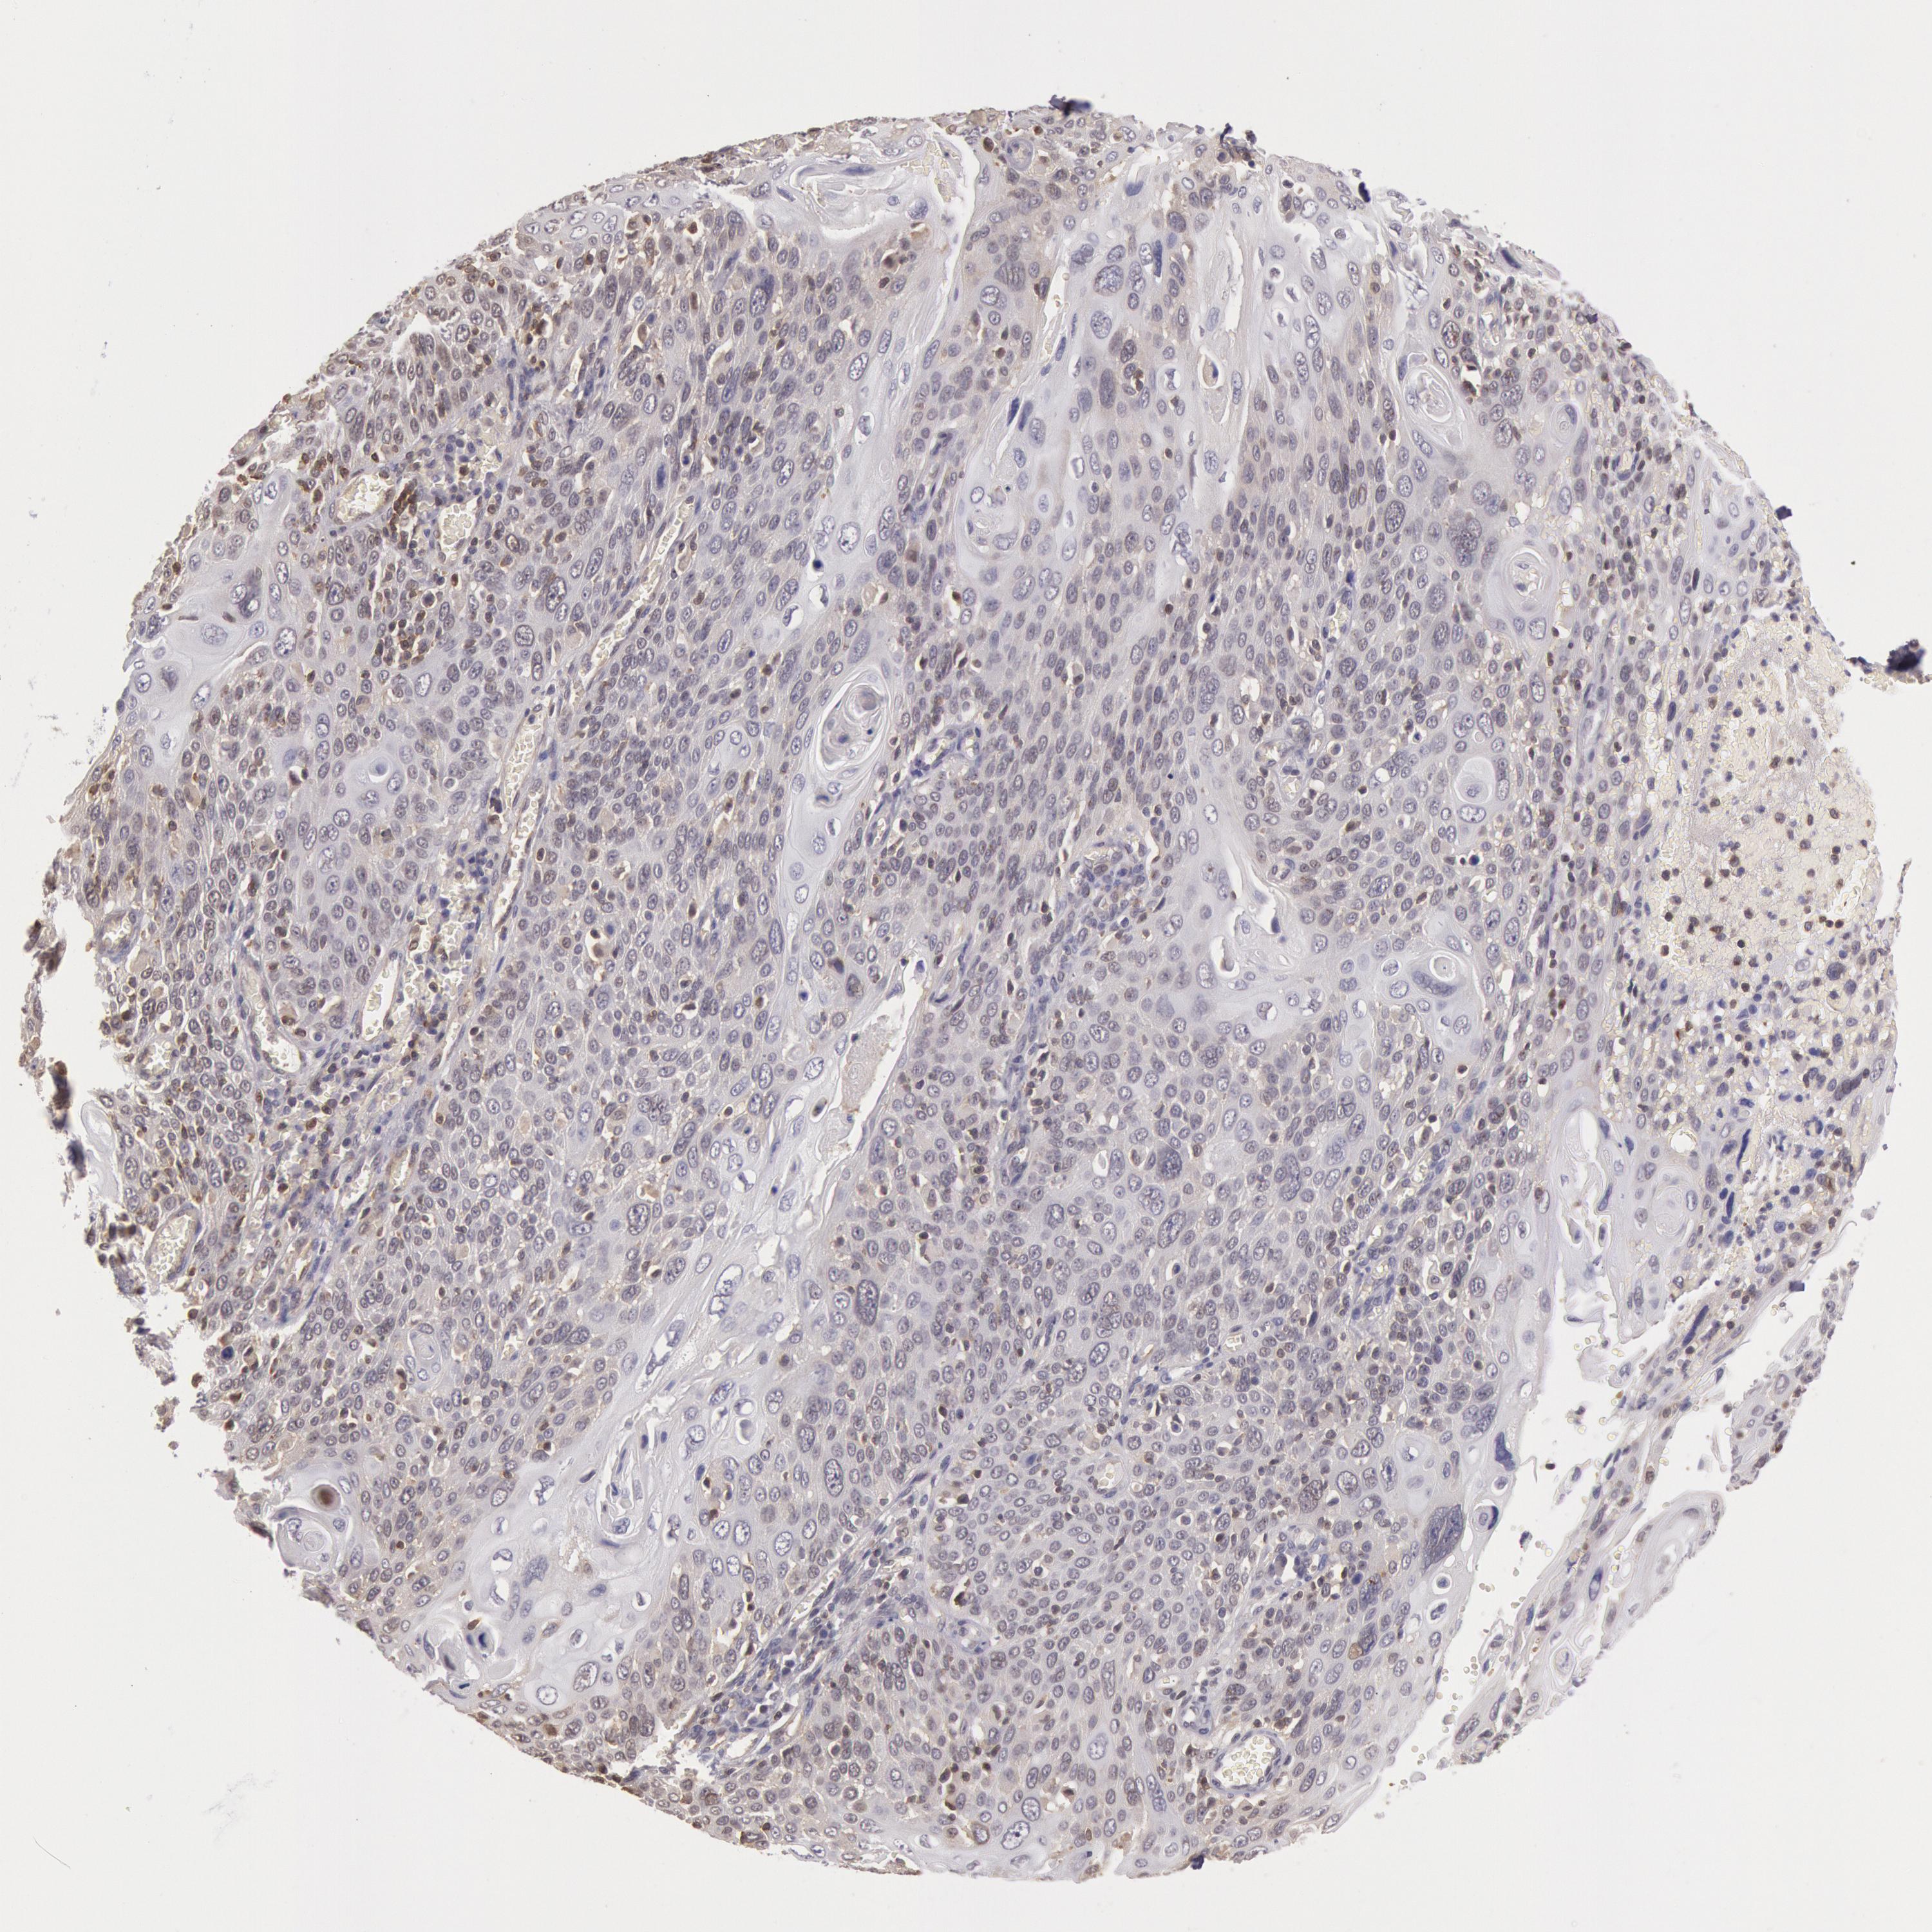

CERVICAL CANCER - Protein expressioni

A mouse-over function shows sample information and annotation data. Click on an image to view it in a full screen mode. Samples can be filtered based on level of antibody staining by selecting one or several of the following categories: high, medium, low and not detected. The assay and annotation is described here.

Note that samples used for immunohistochemistry by the Human Protein Atlas do not correspond to samples in the TCGA dataset.

Antibody stainingi

Antibody staining in the annotated cell types in the current human tissue is reported as not detected, low, medium, or high, based on conventional immunohistochemistry profiling in selected tissues. This score is based on the combination of the staining intensity and fraction of stained cells.

Each image is clickable and will lead to virtual microscopy that enables deeper exploration of all samples and also displays staining intensity scores, fraction scores and subcellular localization as well as patient and tissue information for each sample.

Antibody HPA001275

Antibody CAB017442

Staining

High

Medium

Low

Not detected

Intensity

Strong

Moderate

Weak

Negative

Quantity

>75%

75%-25%

<25%

None

Location

Nuclear

Cytoplasmic/membranous

Cytoplasmic/membranous,nuclear

Squamous cell carcinoma, NOS